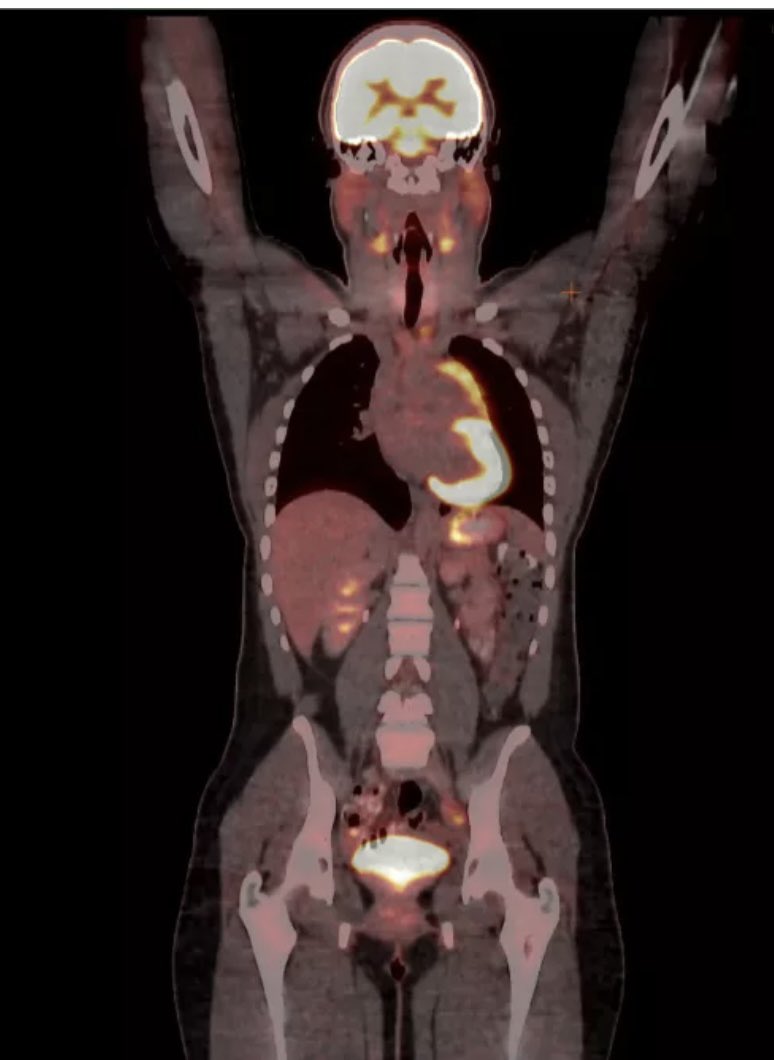

#التصوير_المقطعي_البوزيتروني (#PET)

هذا الفحص يوضح كيفية عمل الأعضاء والأنسجة داخل الجسم. تساعد هذه الفحوصات الأطباء على تشخيص السرطان وعلاجه أيضا يمكنهم رؤية نشاط السرطان والخلايا الأخرى وتتبعها. تشمل ايضا تدفق الدم ومعدل نمو الورم وفعالية أدوية العلاج الكيميائي.☢️

يتم إجراء التصوير المقطعي البوزيتروني (PET) أحيانًا في الوقت نفسه مع فحص #التصوير_المقطعي_المحوسب (#CT). يجمع التصوير المقطعي البوزيتروني- التصوير المقطعي CT صور كل من فحص التصوير المقطعي البوزيتروني والتصوير المقطعي المحوسب ويدمجهم جميعهم مع بعض.

وذالك يوفر للأطباء معلومات عن نشاط السرطان وحجمه وشكله وموقعه في الجسم. يتم إجراء التصوير المقطعي المحوسب أولاً لإنشاء صور تشريحية للأعضاء في الجسم (anatomical) ثم يتم إجراء تصوير مقطعي بوزيتروني لإنشاء صور ملونة توضح التغيرات المتقلبة أو التغيرات الوظيفية الأخرى في الأنسجة.

تستطيع عمليات التصوير المقطعي بالإصدار البوزيتروني (PET) قياس مستوى #الجلوكوز أو #السكر، في الخلايا.

قبل إجراء التصوير البوزيتروني (PET)، يتم حقن المرضى بمادة مشعة - وهي نوع من الجلوكوز يحتوي على قدر ضئيل من المادة المشعة. #FDG_18

نظرًا إلى سرعة نمو #الخلايا_السرطانية وانقسامها، فإنها تمتص أكبر قدر من الجلوكوز مقارنة بالخلايا الطبيعية. تذهب المادة المشعة في اعضاء الجسم ويتم تحديد الخلايا الغير طبيعية وقراءة الصور وتشخيصها من قِبل الدكاترة المختصين.